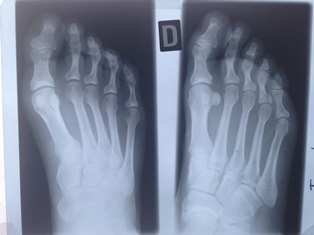

Until the x-ray, all knowledge of human anomalies (apart from visible ones) was limited to those found by anatomists at dissection. But now, new living anatomy was being shown on radiographs.

As this different view of the body came about, the interpretation of shadows had to be made with care. Early radiologists were like aircraft spotters.[ix] Abnormalities of forensic importance were (still are) often subtle and the shadows cast by the new rays could often be confusing. And, of course, what was normal?

By the 1920s, radiology was becoming recognised as a distinct medical speciality. In the 1930s there was a gradual standardisation of projections which culminated in the publication of Positioning in Radiography by Kitty Clark in 1939, which remains in print today.

Radiology, now more commonly referred to as Medical Imaging, has had a huge impact over the last one hundred years. It is now a sophisticated high technology specialty. It has radically changed the way we see our bodies: as full of living tissue, living tissue that sometimes behaves in strange ways. But those strange ways can now be diagnosed and sometimes can be treated. I do not know.